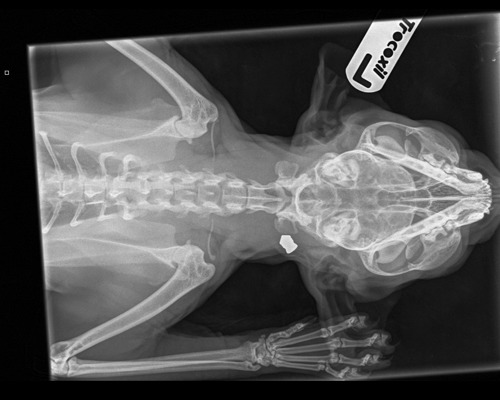

Once Angel was safe and warm, her fosterer began the painstaking task of trying to gently untangle her fur. As she groomed the forlorn cat she discovered a lump on Angel’s neck. Concerned that it might be a cyst or tumour, Angel was taken to the vet where x-rays revealed she had been shot with an air gun and a metal pellet was still lodged inside her. Once the pellet was removed it was revealed as a pointed pellet, most often used for hunting.

Angel's x-ray showing the air gun pellet in her neck